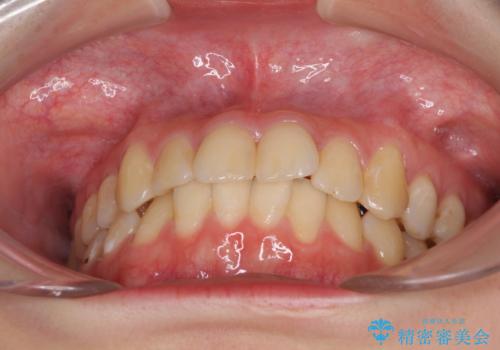

- 上下前歯のデコボコを気にして来院された患者様です。

以前矯正をした後戻りということで、歯列不正はそれほど大きくなかったため、インビザライン・ライトを用いて矯正治療を行うこととしました。

前歯のデコボコが残っており、シミュレーション通りに動いていない部分がありましたが、再矯正であることやご本人の満足いくところまでデコボコが改善されたとのことで、治療を終了することとしました。